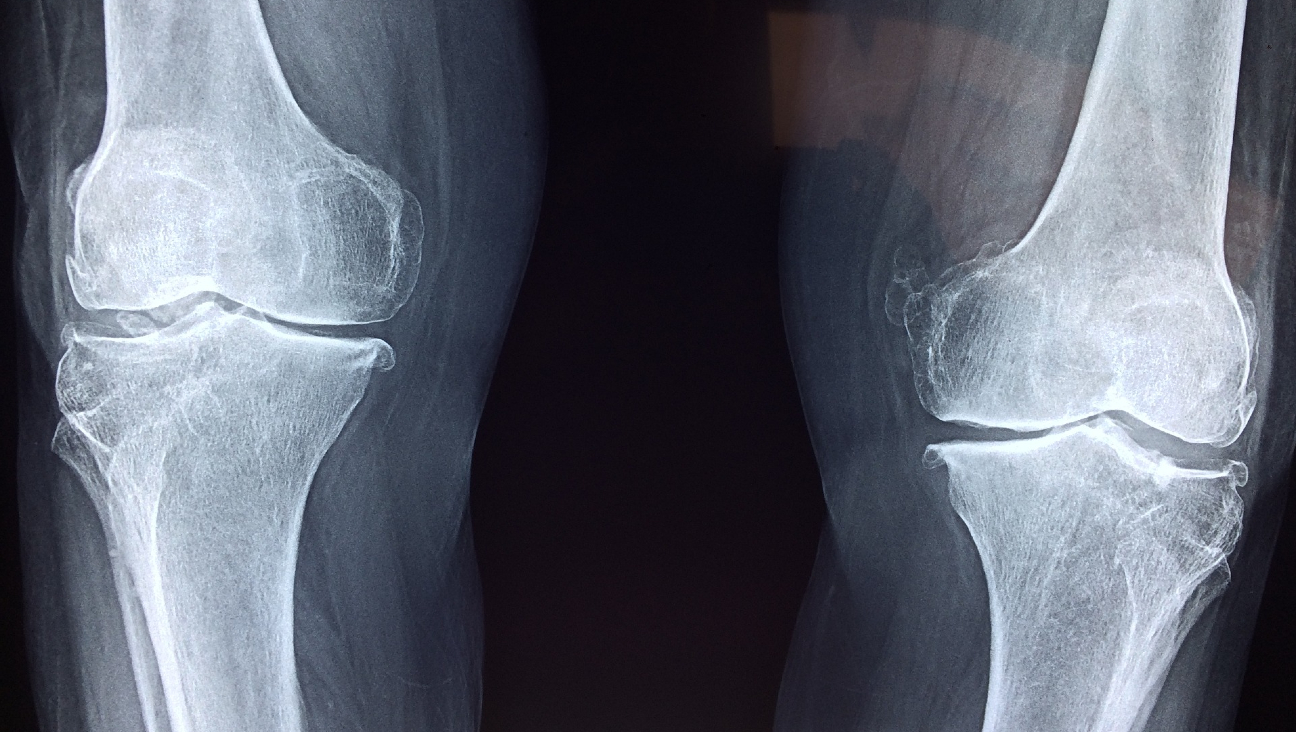

Mensen worden steeds ouder en daarom komen botdefecten steeds vaker voor. Senioren breken namelijk nogal eens een bot bij een valpartij en krijgen vaker een botinfectie. Maar de behandeling is niet ideaal. Onderzoekers van het Pohang University of Science & Technology komen nu met een hydrogel als verbeterde bothersteltherapie, waarover ze publiceerden in het vaktijdschrift Biomaterials.

Bij een botdefect is vaak een bottransplantatie nodig. Dat kan door een stukje bot van elders in het lichaam te halen en die op de plaats van het ‘gat’ te zetten. Maar deze behandeling vergt twee lastige operaties en dat is niet prettig voor de patiënt.